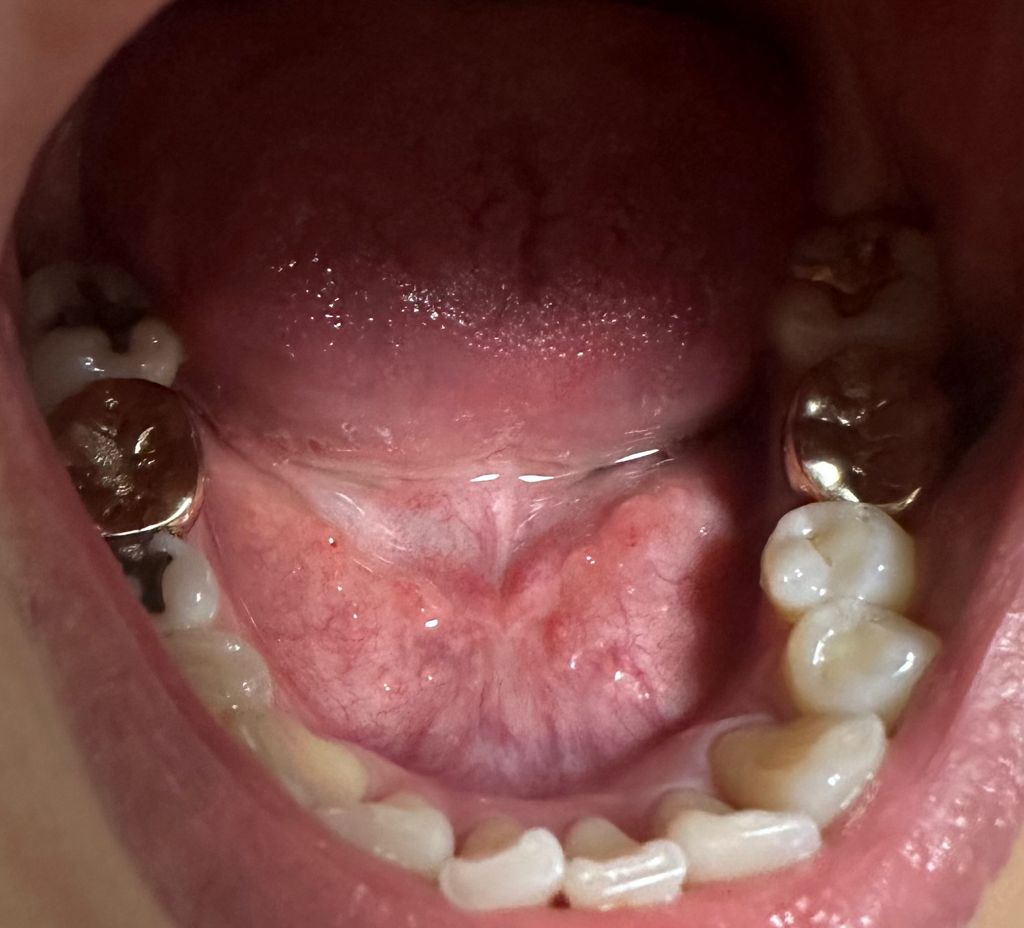

혀 밑이 좀 많이 튀어나와 있는 것 같은데 정상인가요?

어쩌다 혀 밑을 보니 살같은게 많이 튀어나와 있는 것 같은데 제 기준으로 왼쪽이 더 부풀어 있는 것 같아서요

정상적인 모양인지 한번 봐주시면 감사하겠습니다.

• 1번 째 사진